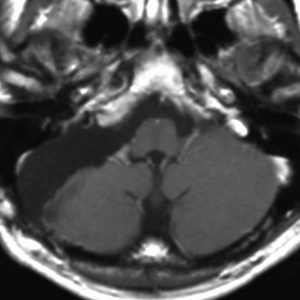

症例:頸静脈孔に限局するもの

小さな頸静脈孔内に限局する神経鞘腫です。無症状で発見されたものであれば,そもそも治療の必要性がありません。多少大きくなっても症状はでません。また手術は侵襲が大きいので,必要があれば定位放射線治療で治療します。定位放射線治療しても何の有害事象(副作用)も出ないものです。